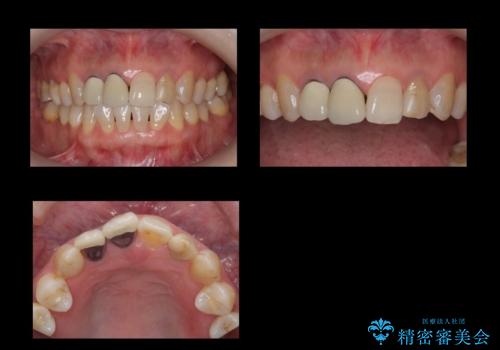

- 前歯のかぶせ物の際が黒いことを気にされて来院。

左上のかぶせ物になっていない歯は根の先に膿がたまっていたので根の治療をし、プラスチックでつぎはぎになっていたためセラミッククラウンでかぶせました。

右上12の二本の根の治療は特に行っておらずクラウンのみやり替えを行いました。